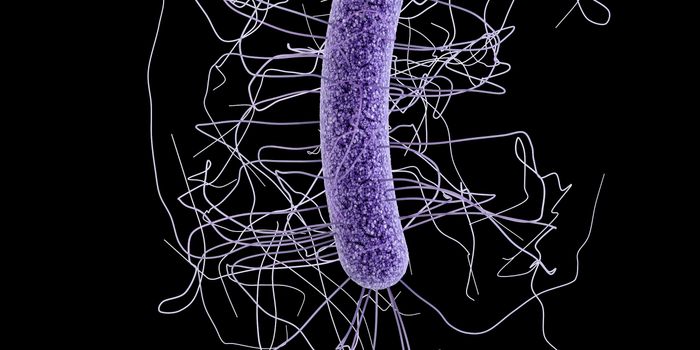

FEB 27, 2015Health & MedicineClostridium difficile (C. difficile, or C. diff) caused almost half a million infections among patients in the United St ...

FEB 27, 2015Health & MedicineATLANTA -- A nasty intestinal bug sickens nearly twice as many Americans each year as was previously thought, according ...

SEP 25, 2015MicrobiologyClostridium difficile is a Gram positive, rod-shaped bacterium commonly found in the soil. However, a small number ...